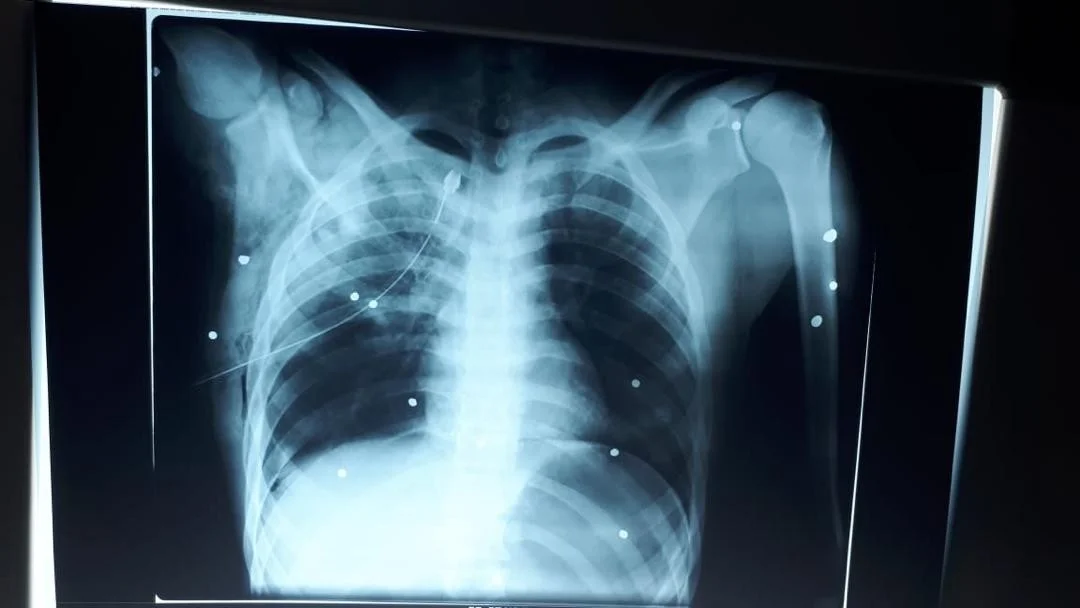

Shotgun pellets 1

Shotgun pellets 2